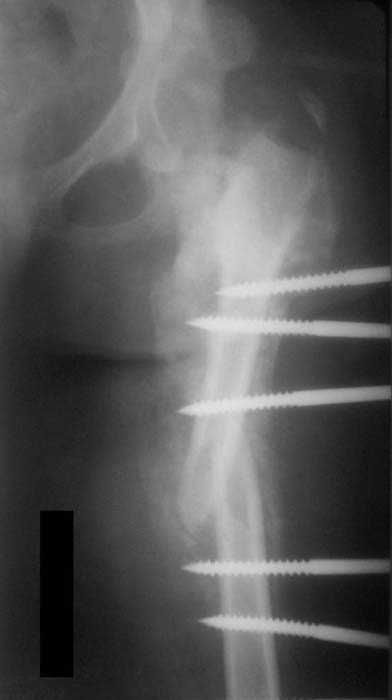

Можно наложить простейший аппарат таз-бедро и подвесить больного (он с ним и ходить сможет), а потом спокойно перемещать лоскуты.

Такая мысль тоже приходила. Не решились, так как:1.Выраженный остеопороз костей таза и бедра, больная тучная - высок риск того, что стержни не выдержат. 2.Сейчас больная передвигается в инвалидном кресле - хоть какая-никакая, а динамизация. Если лишить её этой возможности - застойная пневмония со всеми вытекающими...